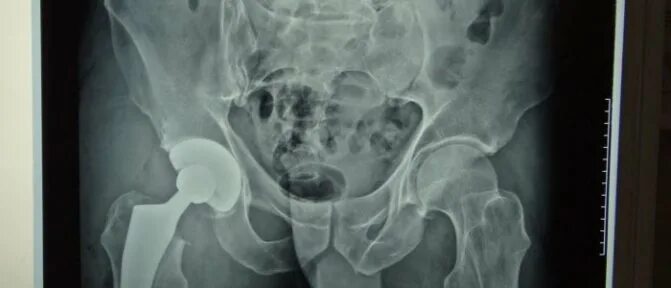

Нестабильность тазобедренного сустава